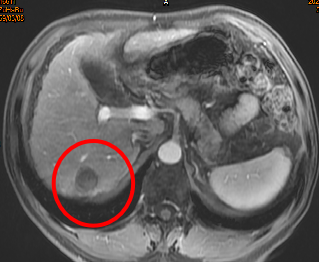

三、原发性肝癌消融治疗

图1:右肝原发性肝癌,直径2.2cm。图2:CT引导下微波消融;图3:术后3个月复查,肿瘤完全坏死;图4:术后1年复查,肿瘤坏死区域进一步缩小,效果满意!